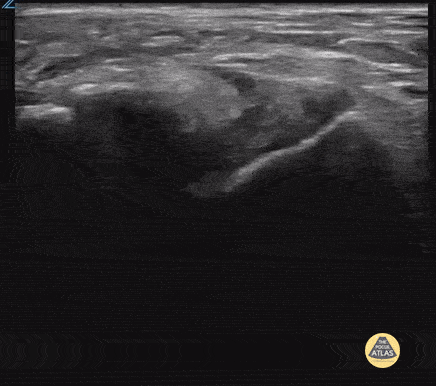

17 yo male inverted his ankle playing basketball. POCUS shows partial tear of the ATFL. Contributor: Paul Khalil, MD Nicklaus Children's Hospital @khalil3paul